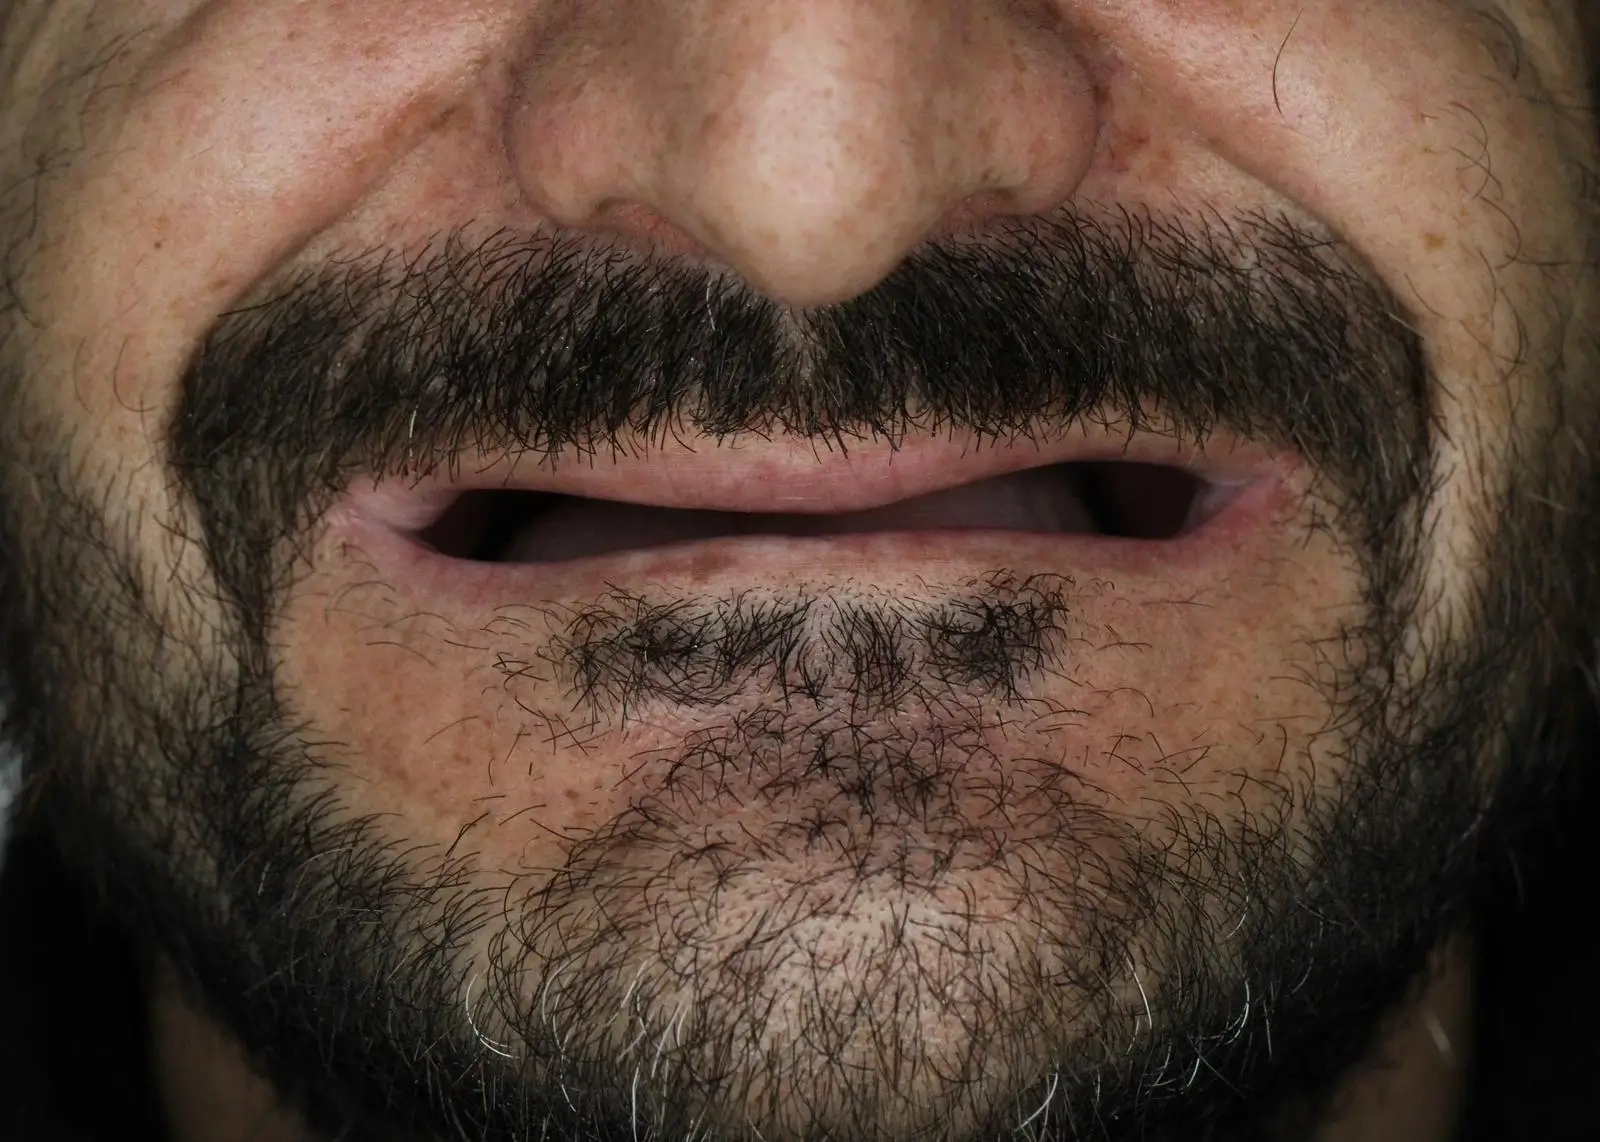

İmplant Üstü Porselen Uygulaması